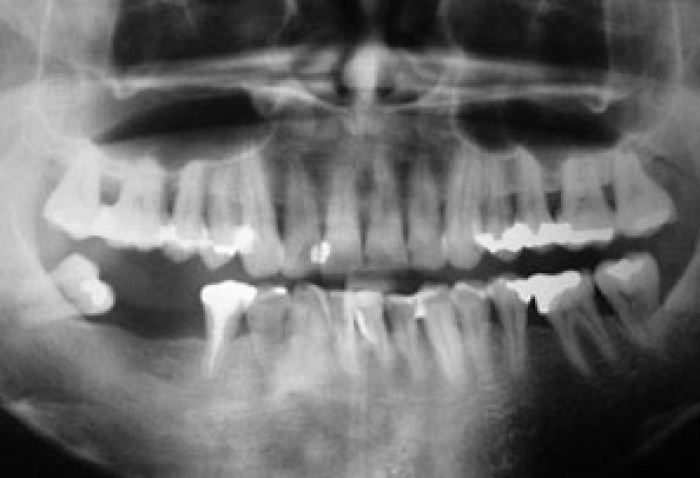

Raio X inicial